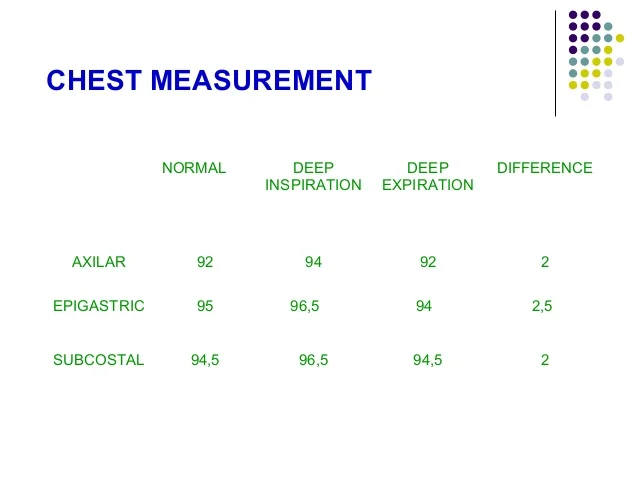

Normal Difference Between Chest Inspiration And Expiration

Normal Difference Between Chest Inspiration And Expiration

More picture related to Normal Difference Between Chest Inspiration And Expiration

Normal Difference Between Chest Inspiration And Expiration - 2025 DIY